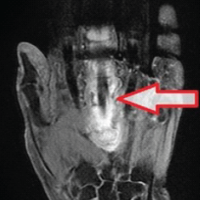

Magnetic resonance imaging on POD 5 was additionally significant for L1-L2 severe right sided neural foraminal narrowing secondary to distracted fragment of L2, at which point the patient was diagnosed with unstable L2 hyperextension fracture and neurosurgery was consulted (Fig. 4).

Figure 4: (Left) Coronal T2-weighted magnetic resonance imaging (MRI) significant for L2 hyperextension fracture. (Middle) Sagittal T2-weighted MRI significant for L2 hyperextension fracture. (Right) Sagittal short tau inversion recovery weighted MRI significant for L2 hyperextension fracture.